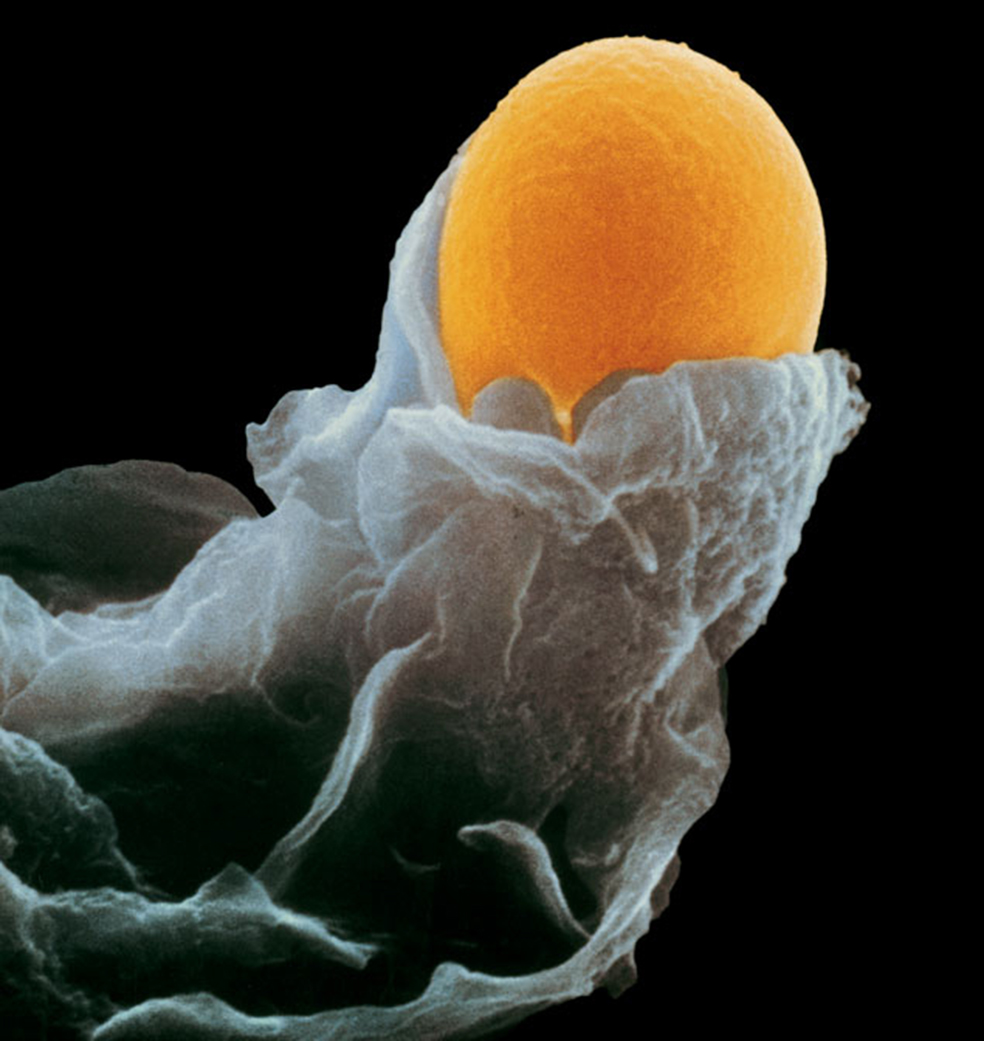

Un óvulo en la trompa de Falopio, donde permanece durante 24 horas, listo para ser fecundado por un solo espermatozoide.

Han pasado entre tres y siete horas desde la relación sexual. Un espermatozoide, entre 300 millones, logra su objetivo: penetrar en el óvulo. Inmediatamente, la superficie de éste cambia para que no entre ninguno más.